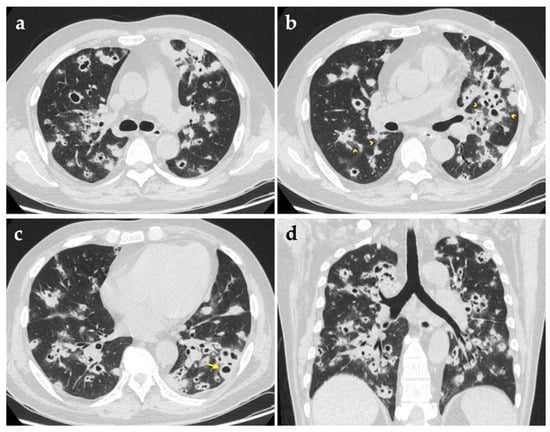

Chest computed tomography (CT) imaging on admission revealed bilateral multiple lung nodules of various sizes, in which some had cavities with thick or irregular walls (Figure 1). Given his critical state of immunosuppression, bronchoscopy was performed, which demonstrated mild mucosal swelling of the dorsal segment bronchus of the left lower lobe, with other segmental bronchi smooth and unobstructed. Bronchoalveolar lavage fluid (BALF) was sent to a variety of microbiological tests, among which routine smears for acid-fast bacilli, fungi and other bacteria, as well as culture for fungi and mycobacterium tuberculosis produced negative results successively. Considering the urgent need for pathogenic information, a metagenomic next-generation sequencing (mNGS) of BALF was ordered as well, and eventually identified 116 sequence reads corresponding to Nocardia cyriacigeorgica. Meanwhile, nucleic acids of another three kinds of pathogens were detected (Table 1). Pneumocystis jirovecii was not considered pathogenically meaningful on account of its poor abundance and not conforming to the patient’s radiological characteristics and would be covered by sulfonamide. Aspergillosis could not be entirely excluded because the antifungal therapy provided before bronchoscopy was likely to interfere with the result of mNGS.

Symptoms of pulmonary nocardiosis are usually nonspecific. Cough with or without expectoration, fever, chest pain, fatigue and weight loss are common and hard to differentiate with other diseases [12]. Radiographic manifestations are important clues for distinguishing pulmonary nocardiosis from other types of pneumonia, tuberculosis or carcinoma. An early study of a few patients indicated that multiple air-space consolidation was the major finding on CT images [13], while a recent study incorporating 25 patients suggested that multiple nodules were the most common imaging manifestation among both immunocompetent and immunocompromised patients [14]. Presentation of single or multiple nodules often mimics malignancy and is difficult to differentiate relying on images alone. Symptoms and correlating laboratory abnormalities with particular clinical history provide crucial hints for diagnosis [15]. In this patient’s imaging, ground-glass opacities around those glaring solid nodules, also known as “halo sign”, may easily be missed but is worth our attention. The halo sign was first described in patients with invasive pulmonary aspergillosis (IPA), usually caused by hemorrhage or inflammatory cell infiltration surrounding the central area of necrosis pathologically. It was found in cases of aspergillosis most frequently, and has also been reported in infections of Mucor, Candida spp., Cryptococcus, herpes simplex virus, cytomegalovirus, Mycobacterium avium complex, Coxiella burnetti and so on [16]. Except for the halo sign, nodules in IPA patients often present a classic air-crescent sign when they develop cavitation and may behave as an important distinguishing feature. Therefore, imaging of our patient failed to favor diagnosis of aspergillosis. Tuberculosis and nocardiosis also have resemblances in CT appearance, and both are more susceptible among immunocompromised hosts, while the absence of lymphadenopathy supported nocardiosis over tuberculosis in our case. It should be noted that Nocardia exhibit varying degrees of acid fastness due to the constituent mycolic acid inside their cell walls, hence further identification of mycobacterial infection and nocardiosis is quite necessary when patients have positive sputum acid-fast bacilli smears. A small study has indicated that the positive rate of conventional Kinyoun acid-fast staining was 57% (13/23) among Nocardia species while that of modified acid-fast staining (using 0.5% sulfuric acid as decolorizer) was 91% (21/23) [17]. Extending time of decolorization may help differentiate Nocardia from Mycobacteria, as the former turn negative. Modified acid-fast staining using 1% or 0.5% sulfuric acid for decolorization is mostly recommended for identifying the Nocardia species [1,17,18].

Figure 1. Computed tomography images on admission. Axial (ac) and coronal (d) high-resolution CT images show bilateral multiple nodules of different sizes with cavities. Some are surrounded by ground-glass opacities (arrowheads) and a few have air-fluid level (arrow). (d) Shows the peribronchovascular predominant distribution of nodules more clearly.